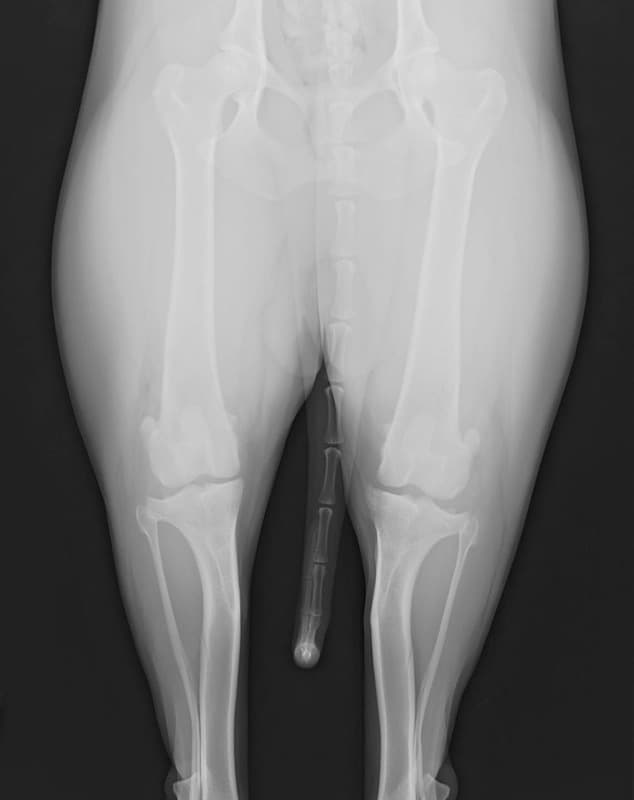

術前正面像